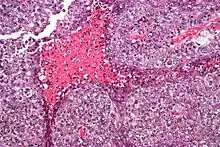

| 显微镜下的胚胎性癌展现出它的一些典型特征:突出的核仁体、标记的核异型、坏疽和核重叠 | |

显微镜下的特征有细胞边界不清、有丝分裂、多样性体系结构(管状乳头状、腺状、实体、胚胎性组织)、核重叠及坏死。去区分它和其他肿瘤(比如精原细胞瘤、畸形恶瘤、卵黄囊瘤和支持-间质细胞瘤)的一类重要特质是,胚胎性癌细胞既有向胚外也有向胚内分化的潜能;比如在睾丸中,这类癌细胞试图形成原始的小管组织。